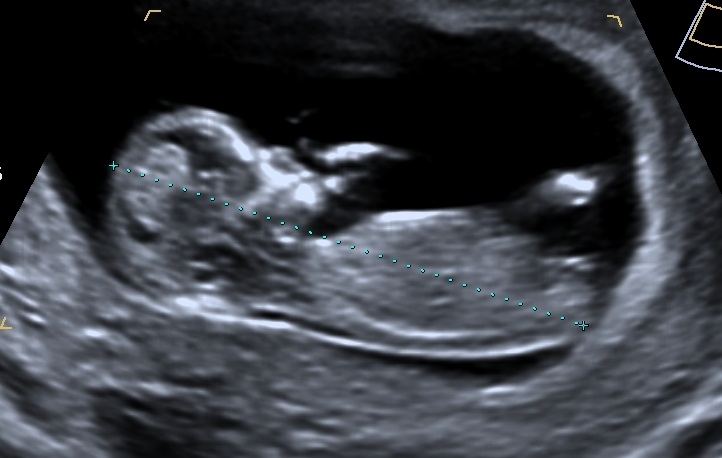

Looks quite girly to me but im no expert, nub seems flat, what are you hoping for?

Looks like a very flat nub... I would say Girl! best of luck!! xo